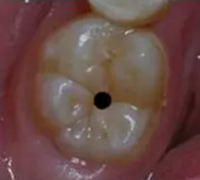

當(dāng)你看到有個小小齲的時候,常常是這樣子的:

當(dāng)心“腹黑”齲齒,牙齒有個小洞也要補(bǔ)!